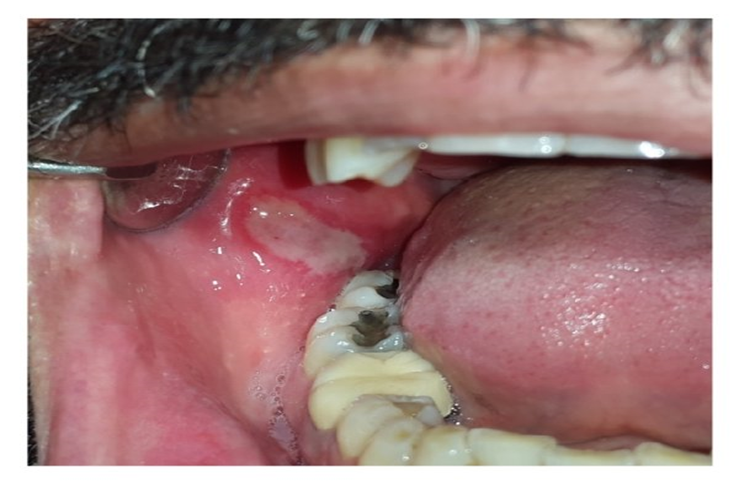

Traumatic ulcer due to teeth

1. Everyday Triggers and Minor Injuries

First, let’s look at the most frequent causes. Many oral ulcers are simply the result of:

- Accidental Bites: Biting your cheek or tongue is a classic trigger.

- Dental Appliances: The sharp edges of braces or dentures can rub against your mouth.

- Aggressive Brushing: Brushing too hard can easily damage the delicate lining of your mouth.